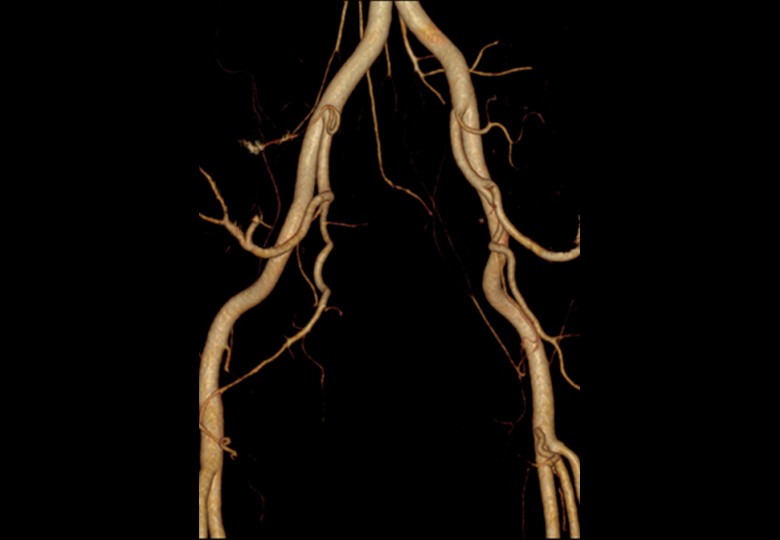

Album d'images cliniques

• Vaisseau